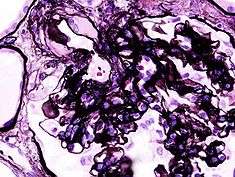

| Histopathological image of diabetic glomerulosclerosis the main cause of nephrotic syndrome in adults. H&E stain. | |